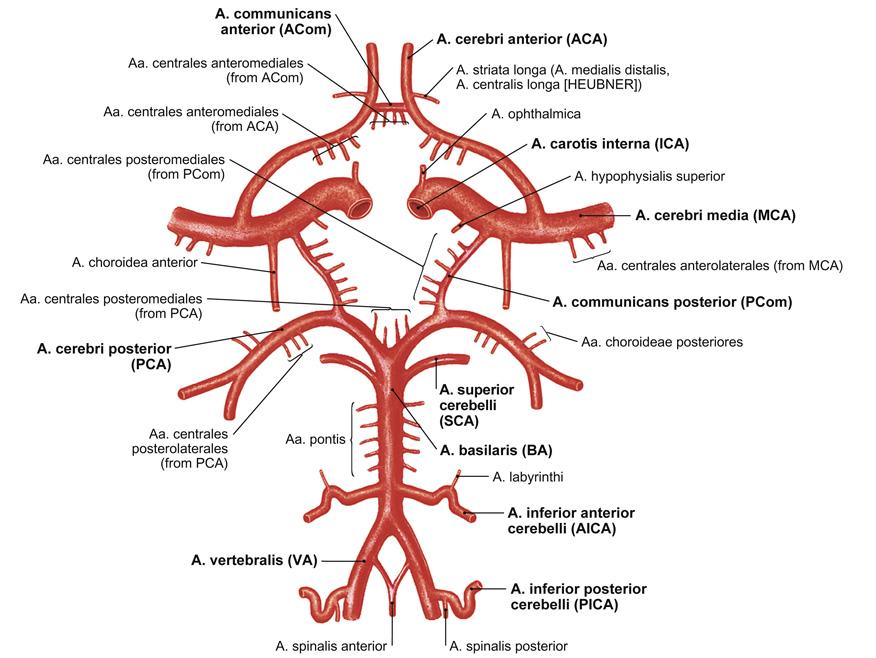

Fig 3.11: a. carotis interna

-

schedelbasis

-

a carotis communis

-

cirkel van Willis

details: zie neuro a vertebralis > a basilaris > a cerebri posterior a carotis interna > a cerebri media a carotis interna > a cerebri anterior a carotis interna > a communicans posterior a communicans anterior